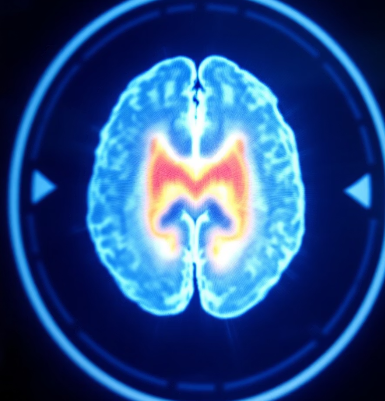

🧠 섬망이란 무엇인가요?

섬망(Delirium)은 짧은 시간 안에 발생하는 급성 뇌기능 장애로, 주로 중장년층 이상에서 발생하며 일시적인 착란, 인지력 저하, 주의력 저하, 의식 혼란을 동반합니다. 특히 입원 환자나 수술 후 노인에게서 흔히 나타나지만 많은 사람들이 단순한 ‘노쇠 증상’이나 ‘치매 초기’로 오해합니다.